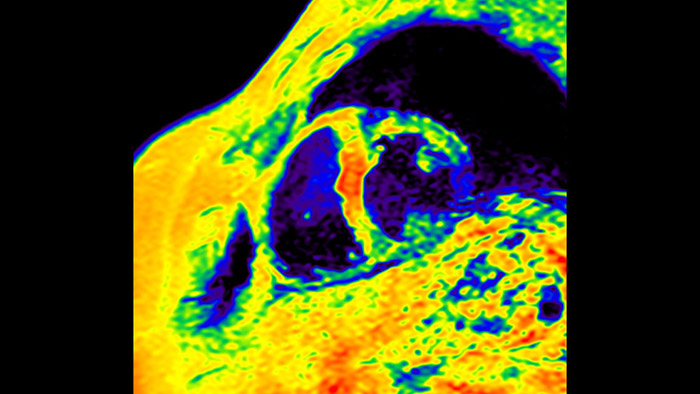

IntelliSpace Portal MR CaaS5,6 Strain7 supporta nella diagnosi e nel monitoraggio dei pazienti fornendo parametri globali di strain, quali strain longitudinale globale (GLS), strain circonferenziale globale (GCS) e strain radiale globale (GRS), utilizzando immagini RM in asse corto e lungo e descrivendo inoltre la deformazione del miocardio, come il suo accorciamento, ispessimento e allungamento durante il ciclo cardiaco.